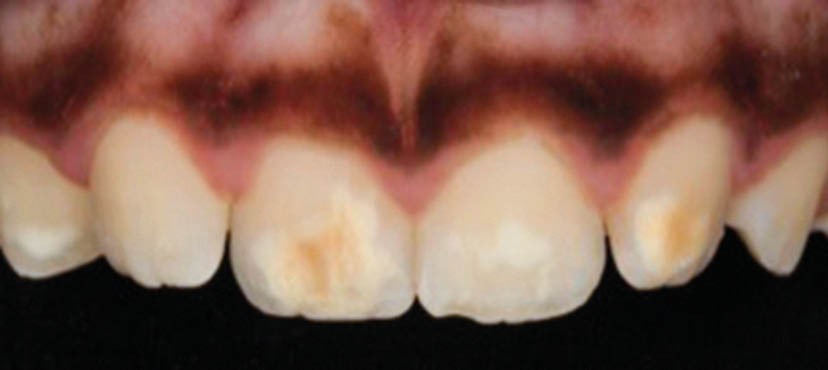

L’émail dentaire, tissu le plus dur et le plus minéralisé du corps humain, peut être affecté par des anomalies génétiques inscrites dans le génome de l’individu, mais également par des facteurs environnementaux. Ces facteurs sont multiples et signent un événement ou une exposition à un xénobiotique au cours de la vie de l’individu. Parmi les atteintes développementales acquises de l’émail, outre la fluorose, figurent les hypominéralisations à type de MIH (Molar Incisor Hypomineralization). Celles-ci sont observées de manière caractéristique sur une ou plusieurs premières molaires permanentes et potentiellement les incisives permanentes éruptant vers l’âge de 6 à 7 ans d’après la description qui en a été faite en 2001 [3] (fig. 1 à 3). La prévalence est importante, la MIH touchant, selon les méta-analyses les plus récentes, plus de 13 % des individus dans le monde, et peut varier selon les études et les pays dans lesquels elles sont menées [4, 5]. Son étiologie est encore incertaine, mais la communauté scientifique s’accorde sur le fait qu’elle serait multifactorielle et notamment en lien avec la survenue d’une hypoxie à la naissance, de fortes fièvres, des épisodes infectieux de la sphère ORL dans la petite enfance ou encore avec une prédisposition génétique [6]. Cette pathologie aurait toujours existé, mais sa prévalence semble être en nette augmentation. Peu d’études ont été réalisées sur cette évolution dans le temps [7].

Les cellules responsables de la synthèse de l’émail, les améloblastes, disparaissant au moment de l’éruption des dents, les défauts de structure et de qualité de l’émail sont irréversibles. L’émail dentaire est ainsi capable d’enregistrer des événements environnementaux ayant eu lieu lors de sa formation. Ces défauts sont donc en quelque sorte le disque dur des contaminations que les améloblastes ont subies. De ce fait, le défaut de minéralisation caractérisant le MIH est le signe d’une exposition environnementale délétère intervenue au cours de la période périnatale (période d’amélogenèse des dents impactées par le MIH), soit environ 5 ans avant leur éruption (fig. 4).

Les leviers à activer dès maintenant pour répondre aux enjeux de santé publique liés à la MIH sont nombreux. C’est d’abord le développement de la collaboration avec les professionnels de santé de la petite enfance. Ceux-ci, dont les médecins généralistes, doivent être sensibilisés au tableau clinique de la MIH – différent de celui de la fluorose ou de l’amélogenèse imparfaite par son caractère asymétrique et sa localisation préférentielle aux molaires et incisives permanentes – afin de favoriser son dépistage et sa prise en charge précoce.